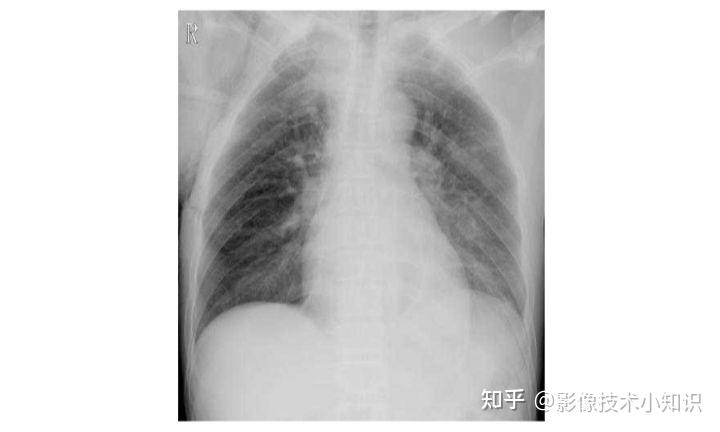

肺挫傷(はいざしょう Lung Contusion)は、胸部の傷害により引き起こされる肺の外傷である。

肺挫傷は、鈍的外力が直接作用することによって引き起こされるが、外傷に関連する爆傷および衝撃波が原因で引き起こされる場合がある。世界大戦における爆薬の使用で、爆破から肺挫傷を生じたため、認知度を高めた。また、交通外傷により同様の衝撃が引き起こされるが、シートベルトとエアバッグを使用することで、危険を減らすことができる。